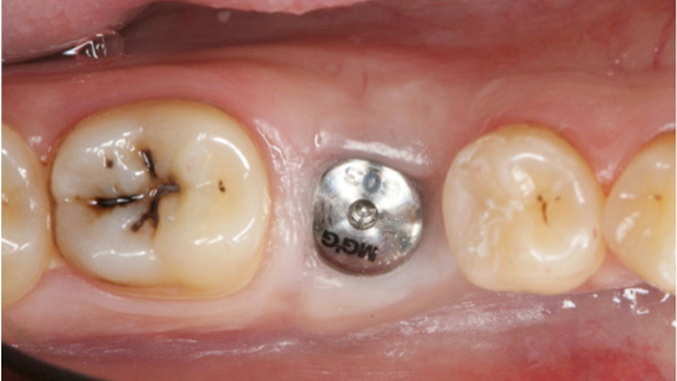

Clinical case: # 46 implant placement & GBR using i-Gen membrane for significant vertical resorption & mixed bone defect

- Courtesy of Dr. Iulian Filipov, Romania -

AnyRidge, mandibular posterior, i-Gen, resorption, bone defect, bone regeneration, space management, #46, GBR, Dr. Iulian Filipov